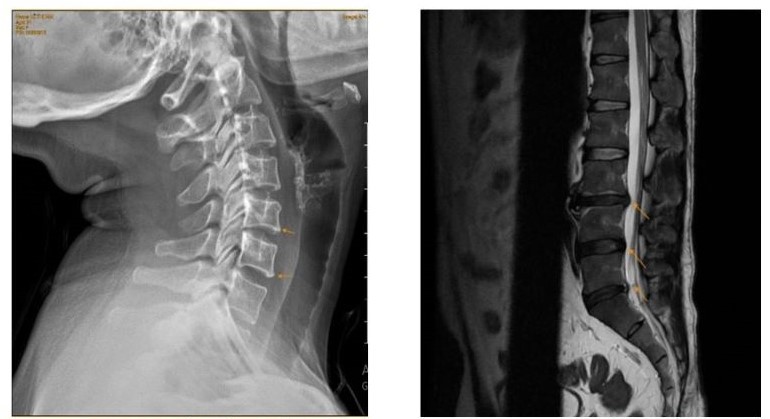

- Kết hợp Đông – Tây y (Y học tích hợp): Đây là xu hướng tất yếu. Tây y dùng để giảm đau cấp tính và chẩn đoán hình ảnh (X-quang, MRI) để phục vụ chẩn đoán; Đông y dùng để điều trị duy trì, phục hồi chức năng và hạn chế tác dụng phụ của thuốc kháng viêm giảm đau.